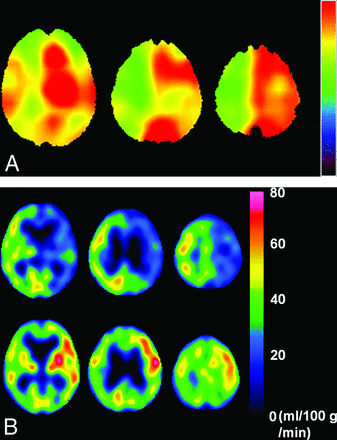

Representative images of the preoperative QSM-OEF maps and the pre- and postoperative quantitative brain perfusion SPECT from a patient with post-CEA hyperperfusion are shown in Fig 4.

A 77-year-old man with symptomatic left internal carotid artery stenosis (85%) who developed cerebral hyperperfusion syndrome with right-sided hemiparesis and aphasia with onset 5 days after the operation. A, Preoperative QSM-OEF images show elevation of the values in the left cerebral cortex compared with those in the right cerebral cortex. B, Brain perfusion single-photon emission CT images before the operation show hypoperfusion in the left cerebral hemisphere (upper row) where hyperperfusion developed immediately after the operation (lower row).